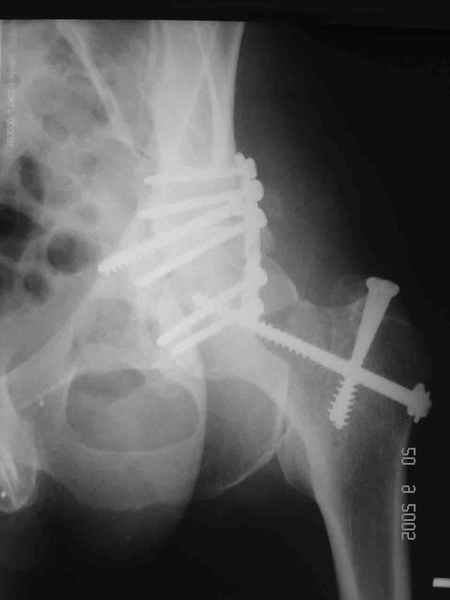

Привет! Вот недавно прооперировали похожий на ваш случай - впадина + шейка (правда у нас впадина поперечный+задний край). После травмы прошло 4 недели. мужчине 46 лет. С такой комбинацией все показания к первичному протезированию. Морально и технически мы к этому уже созрели.Но больной не собрал денег на протез. Выполнили остеосинтез впадины и шейки, прекрасно понимая, что головка вскоре рассосется, мы хотя бы надемся что к этому времени таз срастется, как говорится создали все условия для дальнейшего протезирования (может, и протез в последующем подешевле будет, в смысле, без укрепляющего кольца?). Привет Рункову!

Привет Алекей! Сделано неплохо, поздравляю, хотя второй винтик можно было бы и подлиннее в шейку загнать! Пара вопроов: доступ такой же? головка была свободной или висела на капсуле?

Согласен, можно было и подлиннее. Доступ такой же - чрезвертельный, только разрез кожи прямой (а не Y, чего то я разницы не ощущаю). Головка была абсолютно свободной (то есть во время остеосинтеза таза лежала в стакане и не мешалась). Шансов, что она прирастет 0,00001%. Хотели даже выбросить, но привинтили как временный биологический протез (читай свободный трансплантат), чтоб на период срастания таза бедро проксимально не ушло (может ортопеды потом спасибо скажут). Ну а у вас первичное протезирование при переломе впадины тоже пока полько в планах?